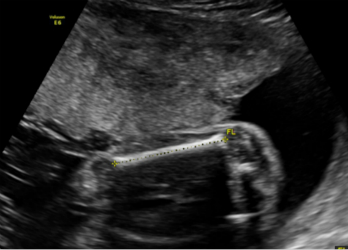

2.妊娠18周~24周超声检查:主要进行胎儿结构畸形的系统筛查。此时期胎儿各器官已发育成熟,系统产前超声检查可记录胎儿各器官结构包括头颅、面部、胸腹腔、心脏、肝脏、双肾、肢体及胎盘等结构,可发现大多数胎儿结构畸形。此阶段是观察胎儿结构和诊断胎儿畸形黄金时段,我们建议所有孕妇在此阶段务必接受一次超声检查。